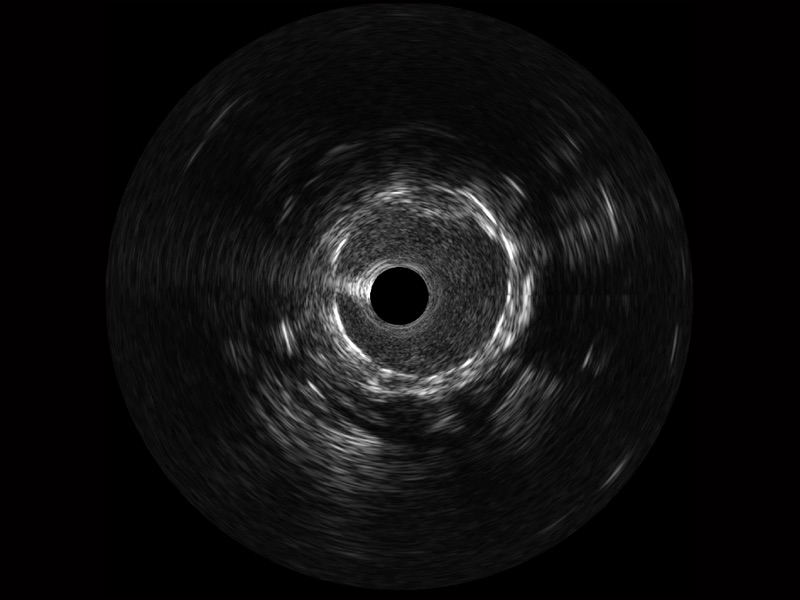

云顶集团官网宽频IVUS图像

传统IVUS图像

对比传统IVUS导管成像,云顶集团官网宽频IVUS图像的近场支架梁显影更细腻,远场中膜外血管仍清晰可辨,兼顾远中近,兼顾分辨力与穿透深度